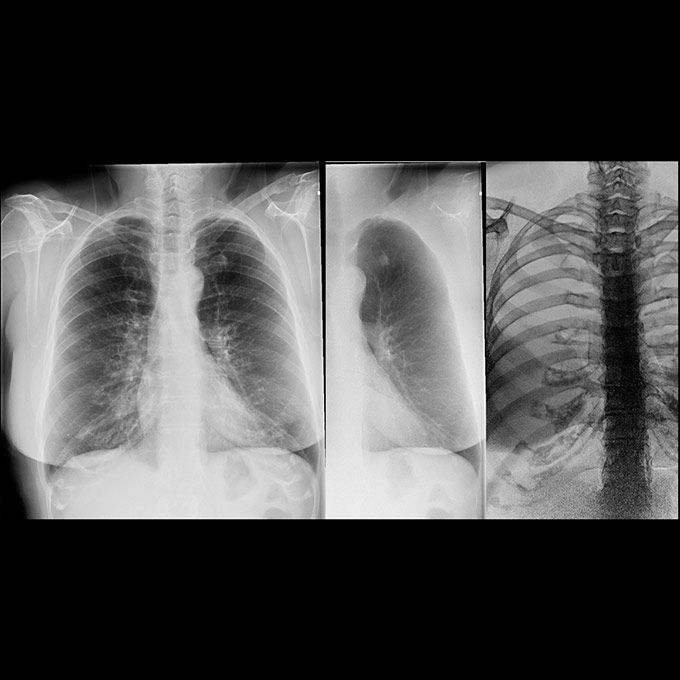

Separate soft tissue and bone structures

Make one acquisition with two exposures at different energy levels in less than 200 milliseconds in chest or abdominal studies.

Process and view the image as a standard radiographic image, an image with bones “subtracted,” and an image of just the bones to highlight foreign objects or calcified structures.